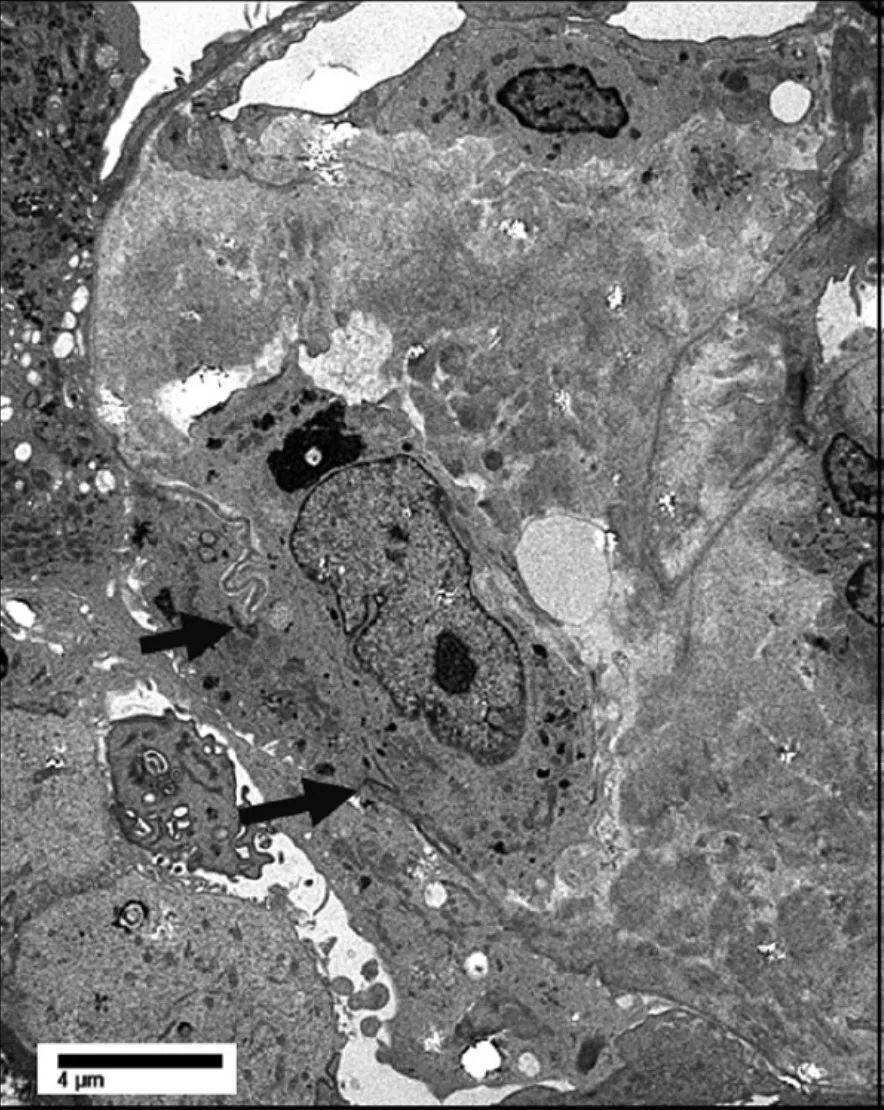

肾小球系膜区域和基底膜广泛的纤维丝,部分基底膜破裂,未见免疫复合物沉积